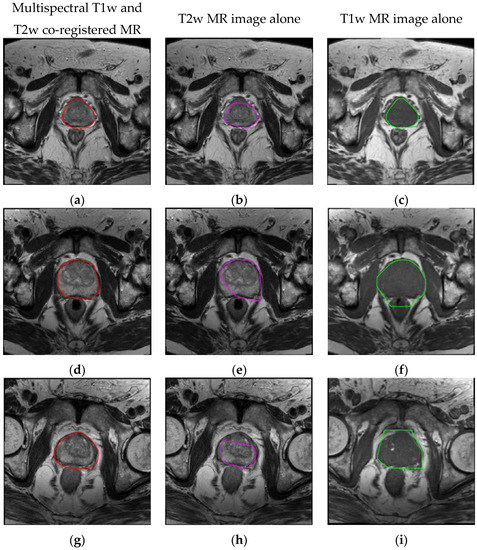

| MRI Data | DSC | JI | Sensitivity | Specificity | FPR | FNR |

| Multispectral | 90.77 ± 1.75 | 83.63 ± 2.65 | 89.56 ± 3.02 | 99.85 ± 0.11 | 0.15 ± 0.11 | 6.89 ± 3.02 |

| T2w alone | 81.90 ± 6.49 | 71.39 ± 7.56 | 82.21 ± 8.28 | 99.63 ± 0.25 | 0.37 ± 0.25 | 12.58 ± 8.49 |

| T1w alone | 82.55 ± 4.93 | 71.78 ± 6.15 | 93.27 ± 4.87 | 98.85 ± 0.58 | 1.15 ± 0.58 | 3.58 ± 4.95 |